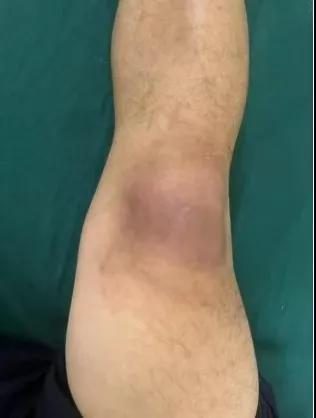

近日,漯河醫(yī)專二附院(漯河市骨科醫(yī)院、漯河市立醫(yī)院)手顯微外科(骨四科)李俊明主任團(tuán)隊?wèi)?yīng)用清熱解毒、拔毒生肌類中藥(骨炎膏)外用結(jié)合抗生素成功治愈一例膝關(guān)節(jié)外傷后軟組織感染病人。

患者,以“外傷致右膝紅腫、疼痛20余天”為主訴就診,20余天前,因騎電車摔傷右膝關(guān)節(jié),致使出現(xiàn)右膝腫脹、疼痛、活動受限,在當(dāng)?shù)蒯t(yī)院給予消腫、止痛治療效果差,繼而出現(xiàn)膝關(guān)節(jié)紅腫熱痛癥狀,門診給予滑膜炎片及消腫止痛藥物治療癥狀未見好轉(zhuǎn),慕名前來我院手顯微外科住院。入院當(dāng)天即給予中藥外敷(骨炎膏),穿刺膿性分泌物送細(xì)菌培養(yǎng),給予廣譜抗生素治療(細(xì)菌培養(yǎng)未出)。

中藥外敷(骨炎膏)主要適用于局部紅腫熱痛,四肢血栓形成、靜脈炎等,具有清熱解毒,拔毒生肌的作用。

中藥外敷骨炎膏給藥直接作用于病灶,彌補(bǔ)了單純口服藥物局部濃度不足的缺陷;同時,中藥外敷與抗生素的系統(tǒng)性抗感染形成"靶向-全身"雙重干預(yù),可顯著縮短療程并降低耐藥風(fēng)險,更為中西醫(yī)結(jié)合治療軟組織感染提供新的思路。(盧 闖 賈煒煒 劉 旭 袁錦鈺)